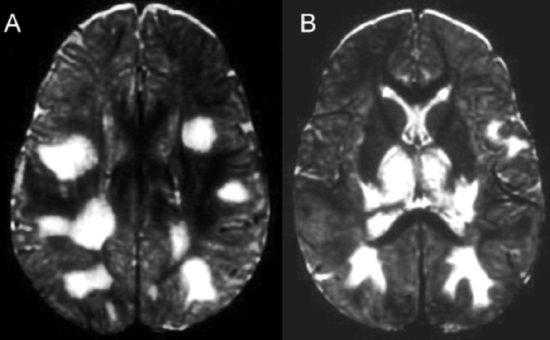

МРТ головного мозга. Аксиальная Т2-взвешенная МРТ. Герпетический энцефалит.

МРТ головного мозга. Тот же пациент. Аксиальная Т1-взвешенная МРТ с контрастированием.

Рисунок 1 | Асимметричные области патологически повышенного МР сигнала в медиальных отделах обеих височных долей, больше выраженные в корковом веществе

Рисунок 2 | В последовательности DWI у того же пациента определяются области повышения сигнала в обоих лобно-височных областях. ИДК подтвердила ограничение диффузии